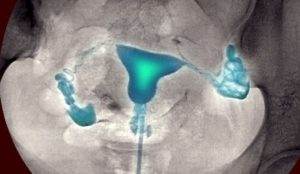

Сущность гистеросальпингографии состоит в заполнении маточной полости и ее труб особым веществом, которое называют контрастным. Вводят его с помощью катетера через влагалище.

Исследование проводят двумя способами: с помощью УЗИ и рентгена. Введенное вещество помогает выявить спайки маточных труб, воспалительные процессы, новообразования.

Второй этап ГСГ УЗИ – установка мягкого катетера в область цервикального канала. На его конце расположен вагинальный датчик, с помощью которого «картинка» попадает на экран монитора. ЭХО ГСГ маточных труб проводится с использованием физраствора.

Им заполняют маточную полость и фаллопиевы трубы. Свободное «растекание» жидкости определяет хорошую проходимость труб.

Если при ЭХО гистеросальпингографии физраствор распространяется неравномерно, это свидетельствует о том, что есть препятствия в виде спаек.

Результаты двух методик с достоверностью «расскажут» о состоянии матки и труб. Расшифровка снимков проста: проходимость маточных труб диагностируется в том случае, если введенное вещество, свободно циркулируя по матке и трубам, выходит в полость брюшины.

Современное медицинское оборудование позволяет провести исследование без использования рентгеновского облучения. Ультразвуковая гидросонография проводится с помощью стерильного физраствора, который вводится в полость матки с применением мягкого катетера для гистеросальпингографии.

Физиологический раствор попадает в полость матки и заполняет фаллопиевы трубы. Врач оценивает этот процесс и контролирует его с помощью трансвагинального УЗИ-датчика. Ультразвук помогает определить, свободно ли жидкость растекается в трубах. При наличии препятствий и нарушенной проходимости жидкость будет распространяться неправильно.